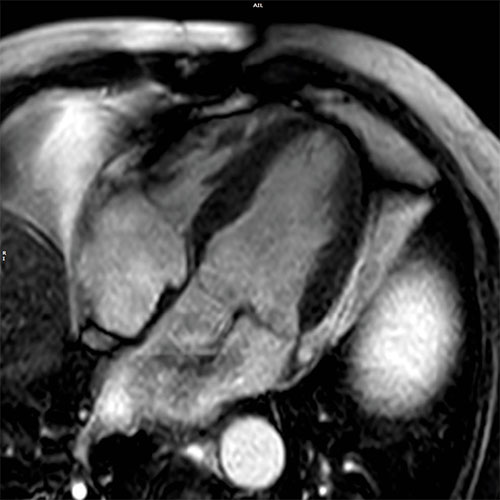

Cardiac MR images of a patient with non-ischemic cardiomyopathy showing delayed enhancement and severe mitral regurgitation.

bTFE - 4 chamber view